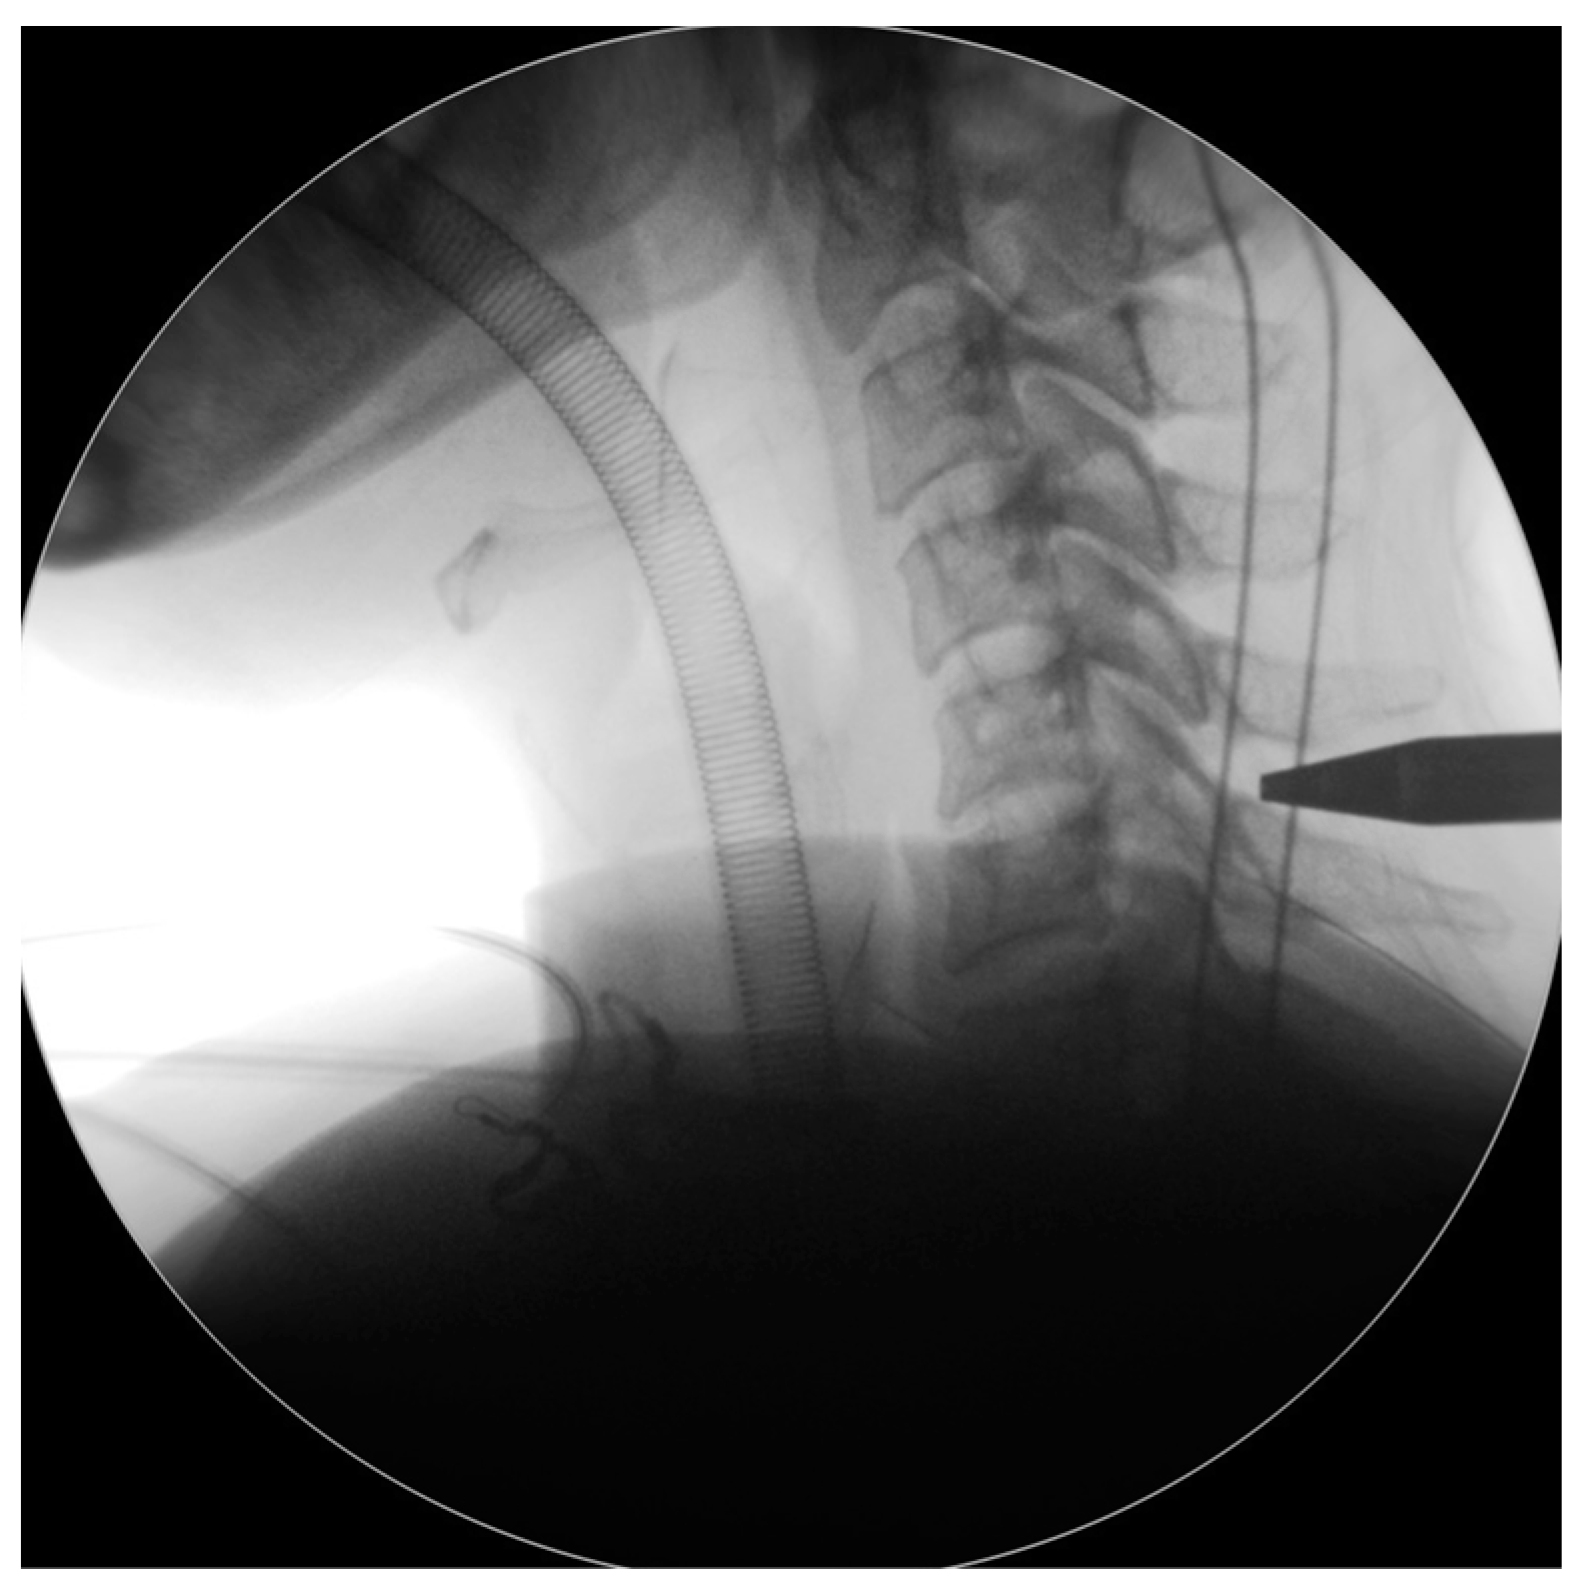

The endoscope was inserted on the dominant side with more intense radiculopathy or myelopathy. A 1-cm skin incision was made near the midline, adjacent to the spinous process, with the precise location confirmed by utilizing both anterior-posterior and lateral fluoroscopic imaging. (Figure 2). We then carefully dissected the fascia through mosquito forceps and passed the muscle layer with a blunt tip dilator. After feeling the edges of the lamina at the targeted spinal level, we placed the working sleeve using the dilator. Then, we rechecked the anterior-posterior and lateral fluoroscopic images after removing the dilator and inserting the endoscope through the working sleeve to ensure its tip landed on the correct level (Figure 3). Likewise, we opted for a 15° endoscope with a 10-mm outer diameter and a 7.1-mm working channel (LUSTA endoscopic system, Spinendos, Germany) to facilitate a more versatile approach to bony decompression through this relatively larger scope.

Figure 2. The incision was made near the midline, close to the spinous process; the level was subsequently confirmed through lateral fluoroscopic imaging.

Figure 3. Check the intraoperative fluoroscopic images to ensure the dilator tip landed on the correct level.